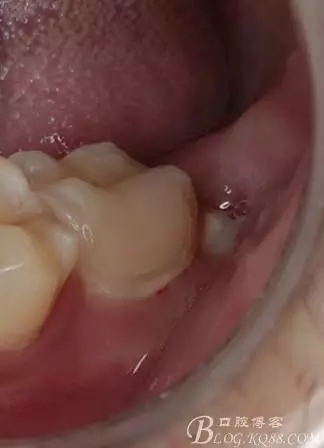

口腔檢查:37頰頜面齲洞,叩(+),探(+),冷熱測試與對照牙對比為敏感。17 27 47 均有不同程度齲壞,無明顯陽性體征。18 28 38 48 呈不同程度傾斜,38 48牙冠部分萌出。全口牙齒排列不整齊,口腔衛(wèi)生較差,牙石(++),部分牙齦發(fā)紅。X線檢查示37牙冠低密度影像累及牙髓,牙周間隙略增寬。

去除暫封物,拍照,比色。